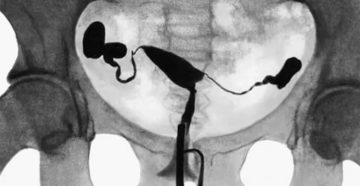

Как проверить проходимость маточных труб правильно Проходимость маточных труб не всегда идеальна. Непроходимость маточных труб…